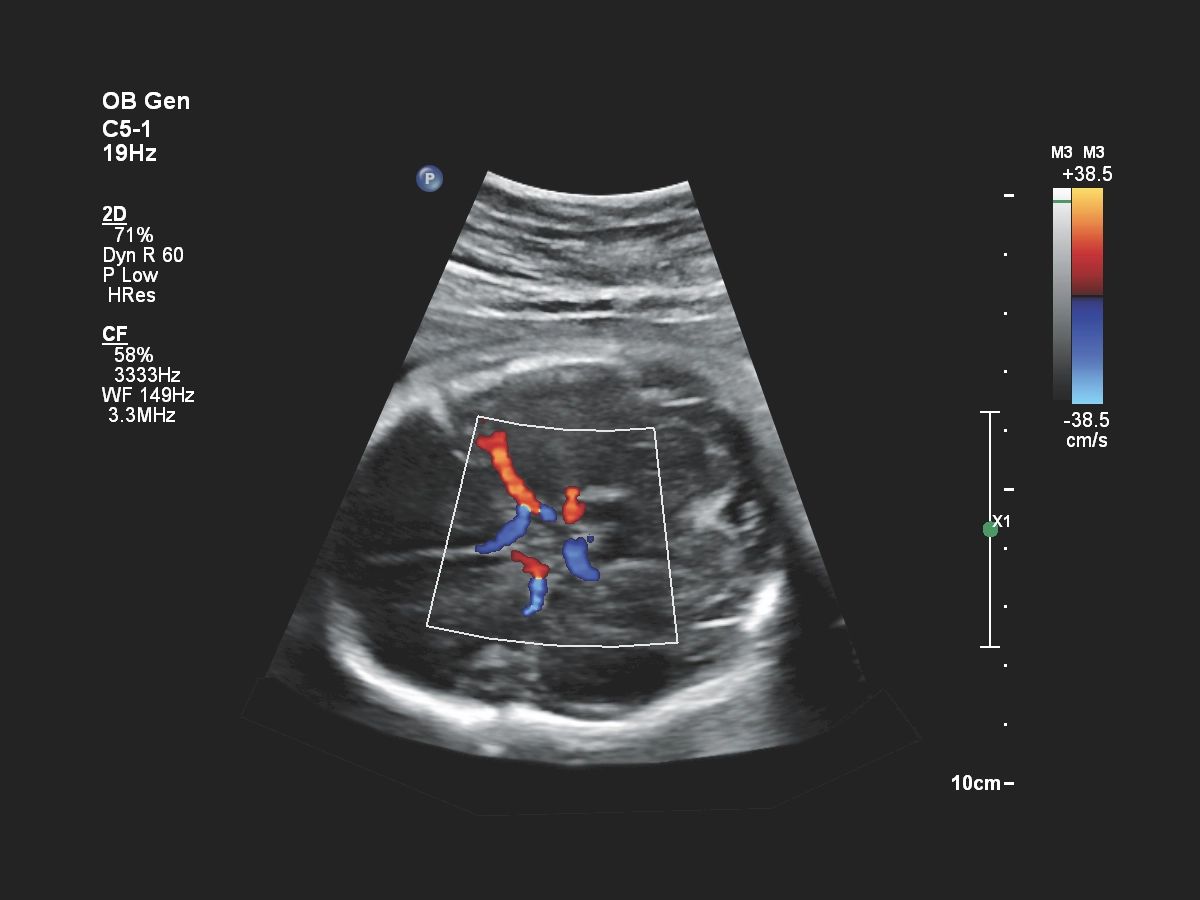

- Акушерство

Функции для гинекологии и акушерства

- Free Hand 3D - возможность реконструкции 3D изображения при помощи линейного или конвексного датчика

- 4D Imaging - автоматическая визуализация 3D/4D изображения

- TrueVue - виртуальный источник света для получения качественного 3D/4D изображения

- FlexVue - опция для визуализации 3D изображений в плоскости

- aBiometry Assist - автоматические биометрические измерения